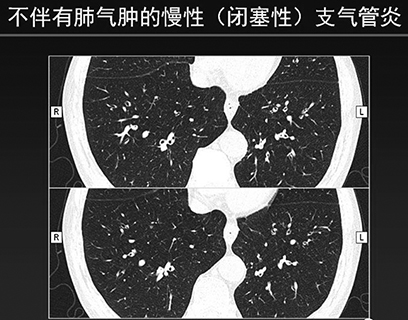

2.氣道病變優勢型︰全肺氣腫指數大於35%,氣道壁厚度大於或等於1.75mm。(如下圖所示)

長久以來,慢支肺氣腫幾乎成了一慢阻肺的代名詞,但有了胸部CT後,根據支氣管壁和管腔的改變,不同類型的肺氣腫已經清晰可辨(如附圖所示),從中也發現了兩者不一定密切相關。所以醫生們必須從影像學角度轉變這個陳舊觀念。同時也要應該清楚一點︰慢性支氣管炎和肺氣腫兩者可以並存,都會導致肺功能下降,但兩者並不存在因果關係。◇